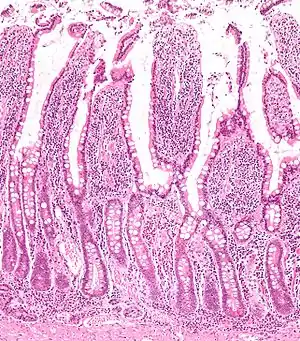

غده رودهای

غده رودهای، کریپت (غدد لیبرکان، خمل یا غارهای لیبرکان) به غدد موجود در لایه اپیتلیال روده باریک و روده بزرگ گفته میشود. کریپتها آنزیمهای مختلفی به مانند، سوکاراز، مالتاز و پپتیدازها را ترشح میکنند.

کریپتهای لیبرکان بر روی تمام سطح روده باریک قرار گرفتهاند. این کریپتها در حدفاصل پرزهای روده هستند. سطوح کریپتها و پرزها از اپیتلیومی متشکل از دو نوع سلول به نام سلول گابلت و سلول رودهای پوشیده شده است. سلولهای گابلت برای روانسازی سطوح روده و حفاظت از آن موکوس تولید میکنند و سلولهای رودهای در کریپتها آب و الکترولیتها را ترشح میکنند و در سطح پرزها، آب و الکترولیتها را به همراه محصولات نهایی هضم بازجذب میکنند. سلولهای رودهای روزانه ۱۸۰۰ میلیلیتر ترشح رودهای میسازند که پیاچ آنها مختصر قلیایی در بازه ۷/۵ تا ۷ میباشد. ترشح آب توسط سلولهای رودهای و بازجذب آب، در جذب مواد مغذی از کیموس ضروری است. علاوه بر سلول های بافت پوششی دارای سلول های بنیادی( stem cell ) و سلول های پانت( paneth cell) و سلول های neuroendocrine هم وجود دارد.